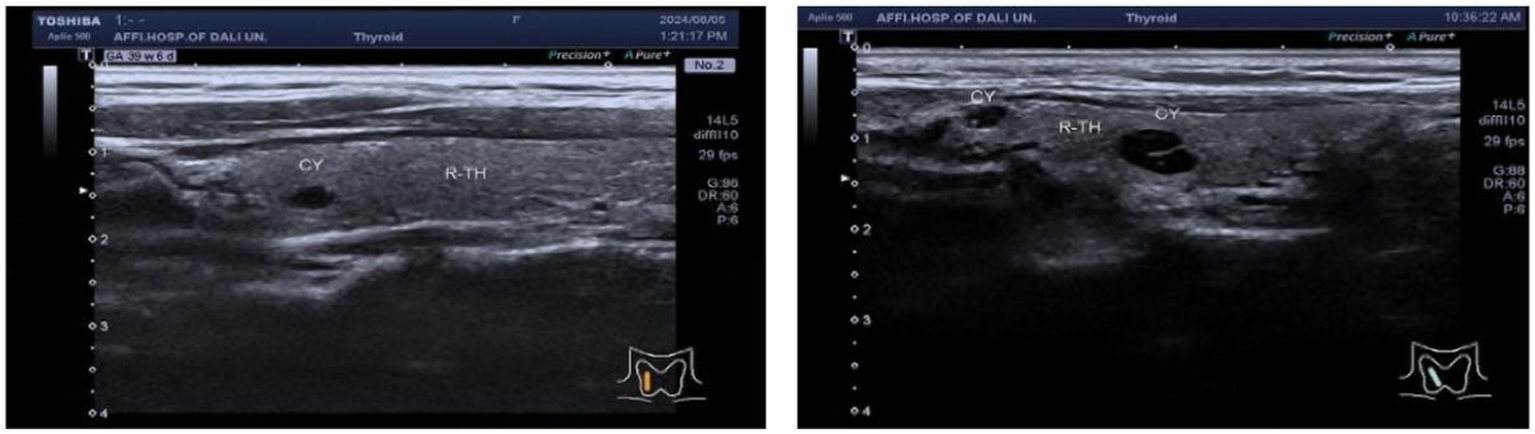

In the TN+ group, comprising 303 patients, the distribution of C-TIRADS classifications among the patients was as follows: 51 cases in class 2, 114 cases in class 3, 59 cases in class 4A, 33 cases in class 4B, 40 cases in class 4C, and 6 cases in class 5.Regarding resilience outcomes, 102 cases were normal, while 201 cases were abnormal, with resilience levels categorized as excellent in 42 cases, good in 60 cases, fair in 77 cases, and poor in 124 cases. The ordered logistic regression analysis revealed that the differences in resilience outcomes were statistically significant [p = 0.044, B = −1.092, OR, 95% CI = 0.327 (0.114–0.943)], indicating that higher c-TIRADS classifications were associated with lower psychological resilience, as depicted in Figure 1. Furthermore, binary logistic regression analysis demonstrated a significant difference in the number of nodules across C-TIRADS classifications [p = 0.005, B = −2.004, OR, 95% CI = 0.135 (0.034–0.537)], as illustrated in Figures 2, 3.

Figure 2

Ultrasound image of cystic nodular lesion in the right lobe of the thyroid gland, C-TIRADS classification: Class 2, multiple cystic nodular lesions in the right lobe of the thyroid gland, C-TIRADS classification: Class 2.